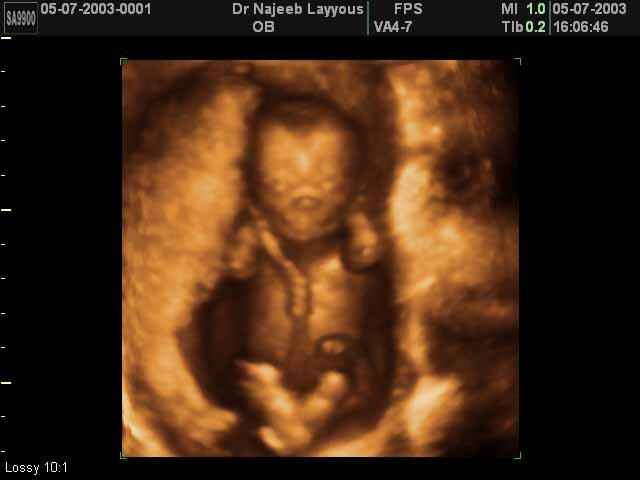

3D First Trimester Ultrasound Scan Photos